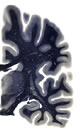

Hi-Resolution Sections · Cells (Nissl Staining) · Virtual Microscopy

Frontal sections (Nissl) from the Atlas Brain: Gallery Slice Single